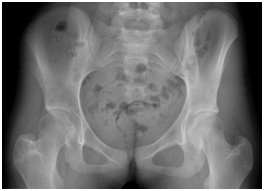

The simple x-ray showed a lytic lesion of the right greater trochanter with well-defined borders and no calcifications within it (Figure 1). The laboratory findings were characteristic of severe protein calorie malnutrition with a normal full blood count and CRP. The magnetic resonance imaging showed signal alteration at the right greater trochanter measuring 3.3 cm in diameter and triangular in morphology, with low signal in T1 and T2. It was well demarcated by a hypointense line and associated with bone marrow oedema of practically the whole of the right neck of femur. We also visualised significant signal changes with acute inflammatory characteristics of the tendons inserting into the right greater trochanter, related to acute tendinopathy in that region (Figure 2).

Figure 1 Initial simple x-ray: lytic lesion of the right greater trochanter.